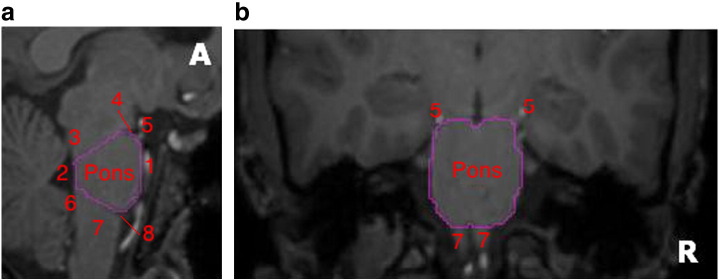

Manual delineation of the pons

Because the pons is not included in the 83 regions obtained via MAPER, we delineated it manually using Analyze 8.1 (Fig. 1).

We evaluated the test–retest reliability of the quantification methods (see “PET data quantification” section) in a selection of eight bilateral ROIs in total. We chose representative regions with high CB1 receptor concentrations; the grey matter masked cortical structures — hippocampus, anterior cingulate gyrus, and inferior frontal gyrus; and the subcortical structures in their entirety, i.e. not grey matter masked (ref. Heckemann et al., 2011) — caudate nucleus, globus pallidus, and nucleus accumbens. In addition, two regions with low concentration of CB1 receptors were evaluated: the thalamus and the manually defined (entire) pons. The data from left and right homologues were averaged prior to quantification.